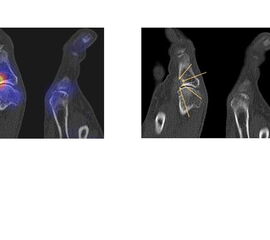

Die Abbildungen 1.5.a bis g zeigen den Infektverlauf nach operativer Korrektur einer Hallux-Valgus-Fehlstellung. Klinisch Weichteilentzündung, im MRT bei V. a. Osteomyelitis zusätzlich zur Weichteilentzündung. Das SPECT/CT wurde zur weiteren Abklärung/Bestätigung der knöchernen Beteiligung angefordert: man erkennt den gelenkbezogenen deutlich erhöhten Knochenmetabolismus im Verlauf des Naviculo-Cuneiformen-Gelenkes (Abbildung 1.5b SPECT/CT, Abbildung 1.5.c CT) und im 2. Lisfranc-Gelenk (Abbildung 1.5.d SPECT/CT sagittal auf Höhe des 2. Lisfranc-Gelenks), Abbildung 1.5.e CT sagittal), dabei CT-morphologisch verwaschene und zum Teil entkalkte subchondrale Grenzlamellen - typisch für eine begleitende (hier infektiöse) Arthritis im Rahmen der ausgedehnten Entzündung mit Osteomeyelitis.

Abbildungen 1.5.f und g: Zur Gegenüberstellung die Bilder im Rahmen der Osteomyelitis/Arthritis (Abbildung 1.5.b und c). Der Befund 1,5 Jahre später (Abbildung 1.5.f und g). Das SPECT/CT wurde zum Ausschluss/Nachweis eines Rezidivs der Osteomyelitis bei erneuten Beschwerden angefordert. Man erkennt wieder einen deutlich erhöhten Knochenmetabolismus im Verlauf des Naviculo-Cuneiformen-Gelenkes; CT-morphologisch jedoch jetzt eindeutig arthrotische Veränderungen bei im Verlauf wieder regelrechter Remineralisierung der Knochenstruktur. Im CT ist sogar im Bereich der subchondralen Geröllzysten zwischen Os naviculare und Os cuneiforme mediale ein Vakuumphänomen im Gelenkspalt zu erkennen, was eine Arthritis praktisch ausschließt. Endgültige Diagnose: postarthritische aktivierte NC-Arthrose, kein Anhalt für das Vorliegen einer Osteomyelitis oder Arthritis.

Bekannte Gicht mit Polyarthralgien. Am rechten Großzehengrundgelenk lateral in der Grundphalanx entzündliche Erosionen.

Gichtarthritis mit Osteolysen und flauen Verkalkungen in den periartikulären Weichteilen/Gelenkkapsel.

Abbildung 1.8.a und b: Akute Arthritis bei bekannter Gicht in beiden OSG: links die Früh-/Weichteilphase; rechts die Mineralisations­phase. Deutliche, entzündlich bedingte Mehranreicherungen in der Früh-/Weichteilphase. In der Mineralisation­sphase erkennt man die entzündliche Mitreaktion der subchondralen Gelenkabschnitte.

Abbildung 1.8.c - e: Akute Arthritis in beiden OSG, rechts > links. Im SPECT/CT erkennt man die Mitreaktion der subchondralen Gelenkabschnitte. Die Arthritis ist so akut, dass (noch) keine ossären morphologischen Veränderungen im CT abgrenzbar sind.